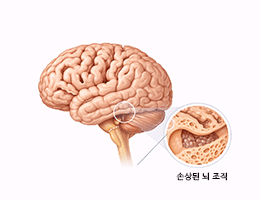

치매 (Dementia)